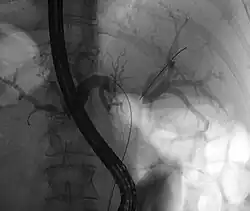

- Endoskopowa cholangiopankreatografia wsteczna (ERCP, ECPW)

Endoskopowa cholangiopankreatografia wsteczna jest pomocna w ustaleniu obecności i rodzaju przeszkody w drogach żółciowych, umożliwia pobranie wycinka lub wymazu szczoteczkowego, co może pozwolić na ustalenie rozpoznania histopatologicznego przed operacją[84][80]. Metoda umożliwia implantację stentów lub protez do dróg żółciowych pozwalających na odbarczenie dróg żółciowych i ustąpienie uciążliwego świądu i żółtaczki[85][89].